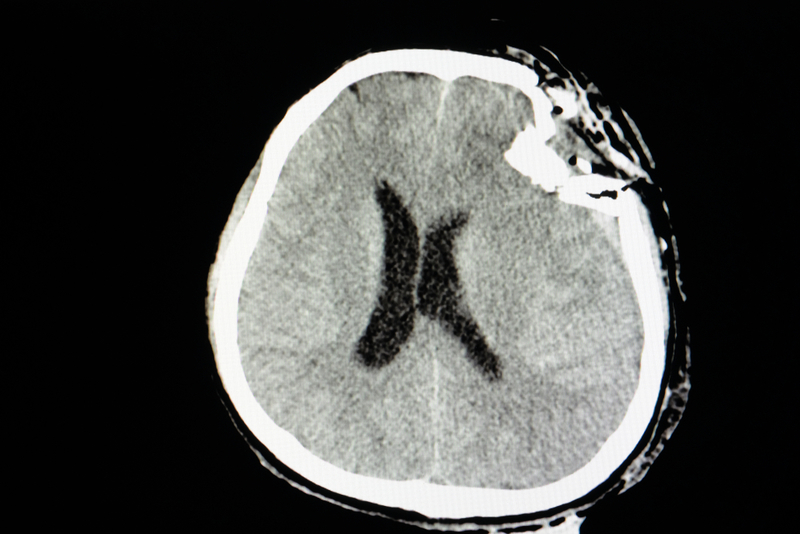

Traumatic brain injury (TBI) or brain trauma results from blows to the head, leading to life-changing disruption of the brain and a cascade of long-term health conditions. A leading cause of disability and death worldwide, TBI may occur due to an open-skull injury, like a gunshot wound, a fall, or an automobile accident. Athletes, the elderly, children, and military service members are particularly vulnerable. Biomarkers are a source of great interest to researchers due to their potential to dramatically improve both the diagnosis and categorization of severity of TBI. Furthermore, they have the potential to validate treatment strategies by indicating whether drugs have reached their proposed targets and achieved therapeutic benefits.

This publication reports the first results demonstrating the ability to use cathepsin B as a blood-based biomarker to capable of identifying TBI severity within different brain regions as well as cerebral spinal fluid. "Biomarker tests that accurately reflect the extent and severity of injury can dramatically improve the standard of care, minimizing the need for resource-intensive diagnostics like CT or MRI scans in favor of more portable tests," said Dr. Angela Boutte, lead author and section chief of molecular biology and proteomics within the Brain Trauma Neuroprotection Branch at WRAIR.

Disclaimer: Image used is for illustrative purposes only and does not represent a true or accurate depiction of the news report.